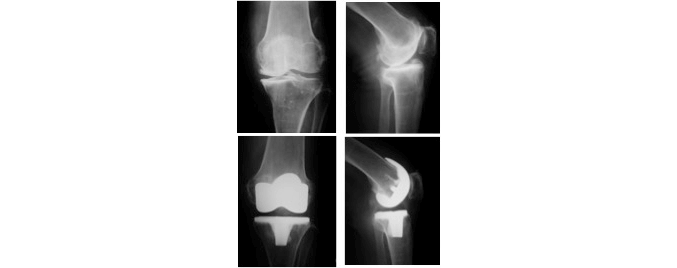

壊れた関節の部分だけを金属とポリエチレンに置換します。

1974年に英国Oxford大学で開発されたモバイル人工膝関節を使用します。すぐれたメニスカルベアリングデザインで、大腿骨側は球構造、脛骨側は平坦であり、膝の全可動域において、ポリエチレン磨耗が最小限となる(年間磨耗量0.03mm。10年成績が98%とすぐれた長期成績を持ちます。

加齢や関節リウマチ、外傷などの原因により高度に障害された関節表面を取り除き、関節部分を金属とポリエチレンに入れ替える手術です。ポリエチレンでできた部分が軟骨の役割を果たし、滑らかに人工関節が動くことができます。

障害された膝関節は人工関節に置換することで痛みが大きく和らぎ、滑らかな動きができるようになり、歩きやすくなります。また、関節の変形も矯正されます。人工膝関節置換術は日常生活の質を高める治療効果の高い手術であると言えます。

以前は膝関節の内側と外側が対称な形状である機種がほとんどでしたが、近年では内側と外側を非対称にして元の膝関節の形状や機能により近くなった機種や、膝の靭帯を全て温存したままで置換できる機種など様々なタイプがあります。患者さんの状態に合わせ、ベストな機種を選び手術を行います。

しかし人工関節置換術における治療の限界もあります。膝関節の可動域は手術前と比べて同じか少し良くなる程度で、劇的な改善は見込めません。また、人工のものであるため、長い間使用し続けることでゆるみや摩耗が生じます。そのため耐用年数は永久というわけにはいかないため、一般には60歳以上が適応年齢となります。さらに耐用年数には個人差があるため、経年的にゆるみがひどくなり再置換術が必要にある場合があります。